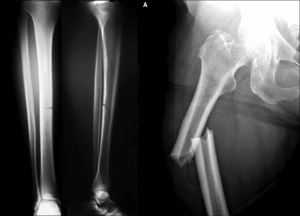

Patah Tulang Pinggul

Patah tulang pinggul adalah salah satu komplikasi paling serius dari osteoporosis, terutama pada lansia. Pemulihan bisa memakan waktu lama dan sering kali memerlukan operasi.

Patah Tulang Belakang

Fraktur pada tulang belakang dapat menyebabkan sakit punggung kronis dan perubahan postur tubuh yang semakin membungkuk.